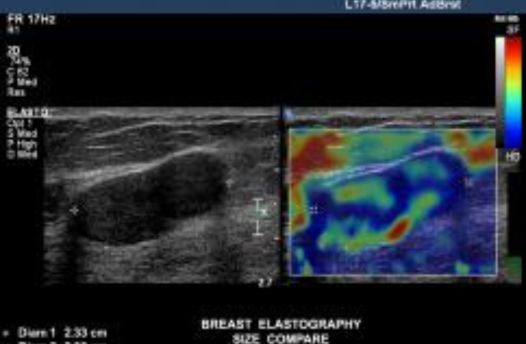

Ελαστογραφία Μαστών

Με το έγχρωμο υπερηχογράφημα υψηλής ευκρίνειας των μαστών αναδεικνύεται η βλάβη σε αρχικό στάδιο, αποτυπώνεται η μορφολογία της, οι αιμοδυναμικές παράμετροί της και η σχέση της βλάβης αυτής με τους γύρω ιστούς. Τα μορφολογικά και αιμοδυναμικά χαρακτηριστικά της βλάβης σε ορισμένες περιπτώσεις δεν είναι αρκετά για τον χαρακτηρισμό της βλάβης σε καλοήθη ή κακοήθη.

Εκεί έρχεται να βοηθήσει η ελαστογραφία, που γίνεται ταυτόχρονα με το υπερηχογράφημα των μαστών προσθέτοντας επιπλέον κριτήρια για τον χαρακτηρισμό της βλάβης. Η ελαστογραφία είναι μία νέα και ιδιαίτερα χρήσιμη τεχνική επιτρέπει την αξιολόγηση της σκληρότητας των ιστών. Ορισμένες παθήσεις, όπως ο καρκίνος, οδηγούν στην αύξηση της σκληρότητας των ιστών. Ένας φυσιολογικός ιστός δηλαδή, έχει ελαστικά χαρακτηριστικά, ενώ ο νεοπλασματικός ιστός παρουσιάζει σκληρότητα.

Η ελαστογραφία παρουσιάζει μία αναλογία με την ψηλάφηση που εκτελείται από τους κλινικούς γιατρούς για ανίχνευση αλλοιώσεων στον μαστό, με τη διαφορά ότι η κλασική ψηλάφηση είναι μία υποκειμενική εξέταση και εμφανίζει μικρή ευαισθησία στην ανίχνευση των μικρών αλλοιώσεων ειδικά όταν βρίσκονται σε μεγάλο βάθος από την επιφάνεια του δέρματος. Με την ελαστογραφία λαμβάνονται πληροφορίες για την ελαστικότητα της βλάβης όσο βαθιά κι αν αυτή βρίσκεται.

Πολλές μελέτες αποδεικνύουν ότι η ελαστογραφία, αποτελεί, το 2ο κριτήριο με το οποίο μπορούμε να χαρακτηρίσουμε αν ένα υπερηχογραφικό εύρημα είναι καλοήθες ή κακοήθες βάση της σκληρότητας του.

Ο συνδυασμός υπερηχοτομογραφίας και ελαστογραφίας έχει σαν στόχο την καλύτερη ανίχνευση και τον χαρακτηρισμό του όγκου, με αποτέλεσμα την αποφυγή περιττών βιοψιών, γιατί με την ελαστογραφία μπορούν να μειωθούν οι μη απαραίτητες βιοψίες σε καλοήθεις βλάβες, οι οποίες μπορούν απλώς να μπουν σε παρακολούθηση.